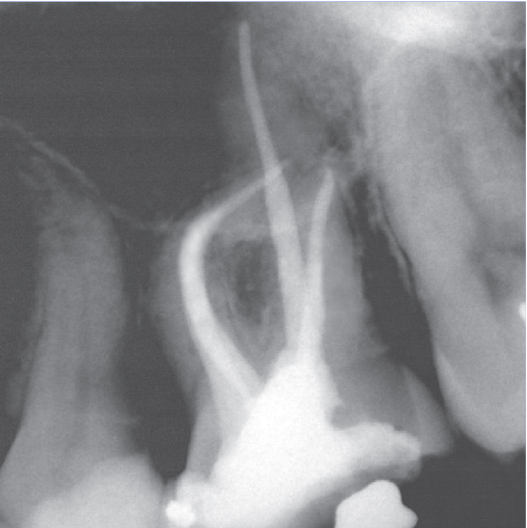

Before

Before Root Canal treatment